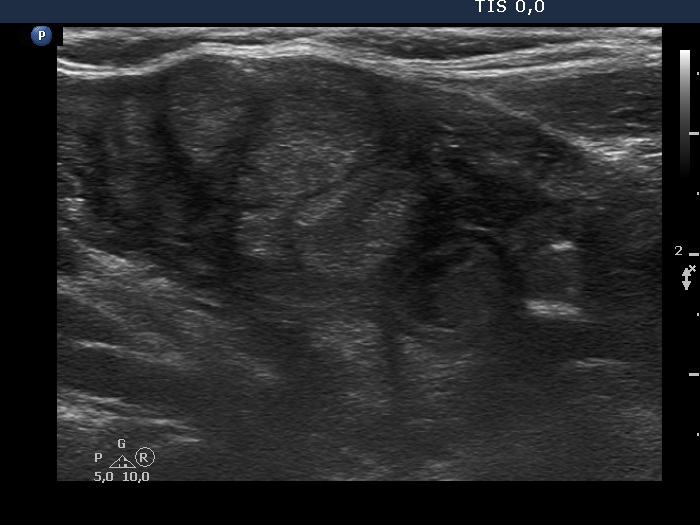

Discrete lesion or nodule in Hashimoto's thyroiditis - case 28 (1124) (ultrasonographic picture 4)

Lower part of the right lobe, longitudinal view. Here we can see an area with micronodular pattern. The origin of these lesions is doubtful.